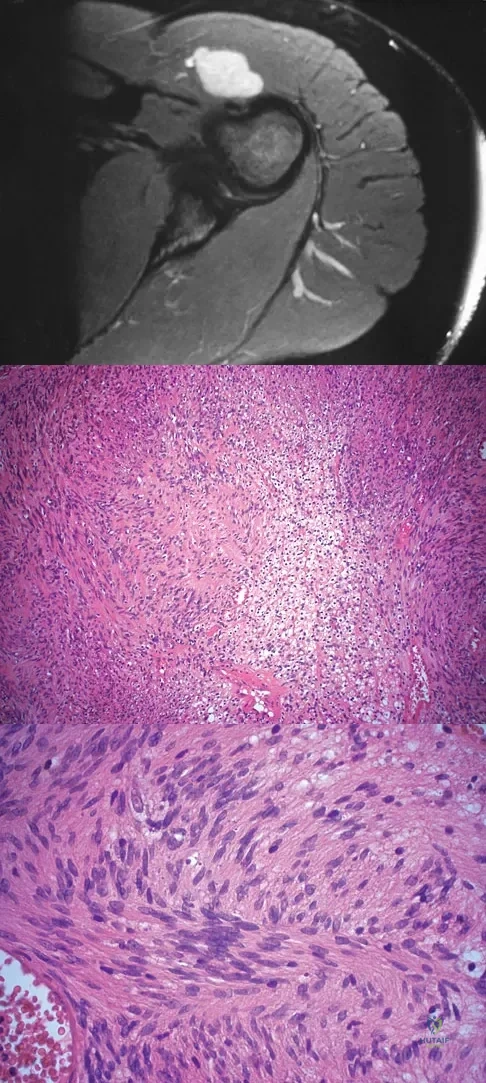

A 28-year-old woman has left shoulder pain and a tender soft-tissue mass. Based on the MRI scan and biopsy specimens shown in Figures 74a through 74c, what is the most likely diagnosis?